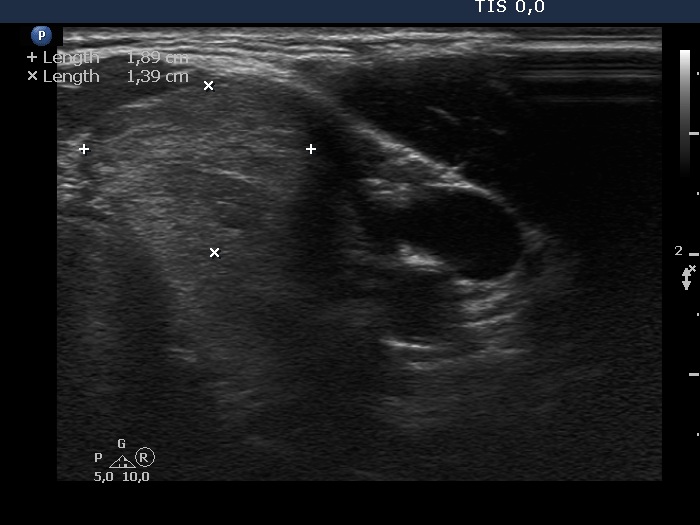

Ethanol sclerotherapy: non-toxic solid nodules - Case 5

Fourteen years after the therapy (ultrasonographic picture 3)

Upper part of the left lobe, horizontal scan. The upper part of the previously treated nodule did not change in size.